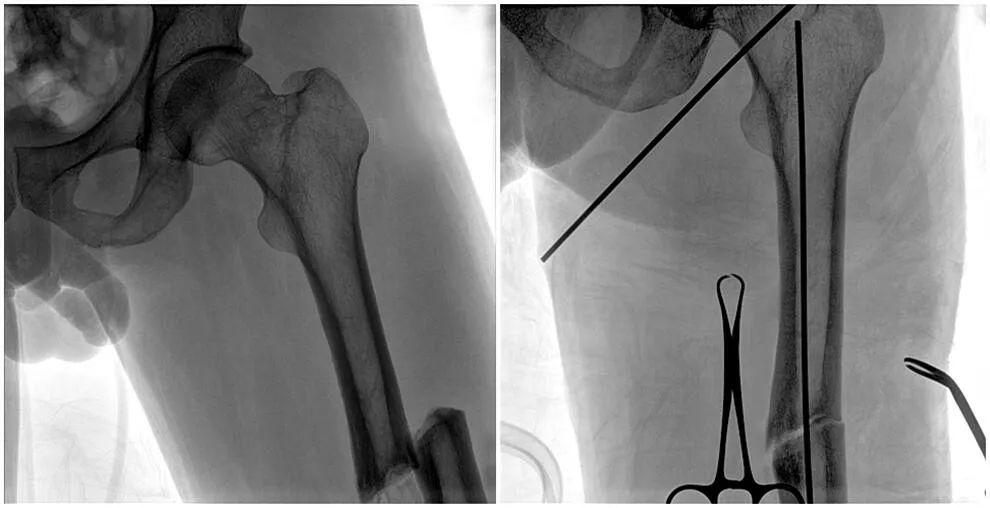

C形臂輔助手術(shù)過(guò)程

術(shù)中使用普愛(ài)醫(yī)療大平板一體式C形臂進(jìn)行透視,判斷骨折情況及克氏針、髓內(nèi)釘?shù)冉饘僦踩胛锏奈恢?,進(jìn)行調(diào)整。C形臂準(zhǔn)確的術(shù)中定位,大大縮短了手術(shù)的時(shí)間,減輕了患者的痛苦,輔助手術(shù)順利完成。

在進(jìn)行髓內(nèi)釘內(nèi)固定術(shù)時(shí),醫(yī)生需要同時(shí)觀察到入釘點(diǎn)和骨折部位的情況,普愛(ài)醫(yī)療大平板一體式C形臂采用30CM×30CM的平板探測(cè)器,能夠呈現(xiàn)更廣闊的成像面積,滿足大部分長(zhǎng)骨髓內(nèi)釘內(nèi)固定術(shù)的攝片需求。

術(shù)中定位準(zhǔn)確、出血量少,術(shù)后影像顯示股骨移位糾正,恢復(fù)良好力線,手術(shù)效果良好。